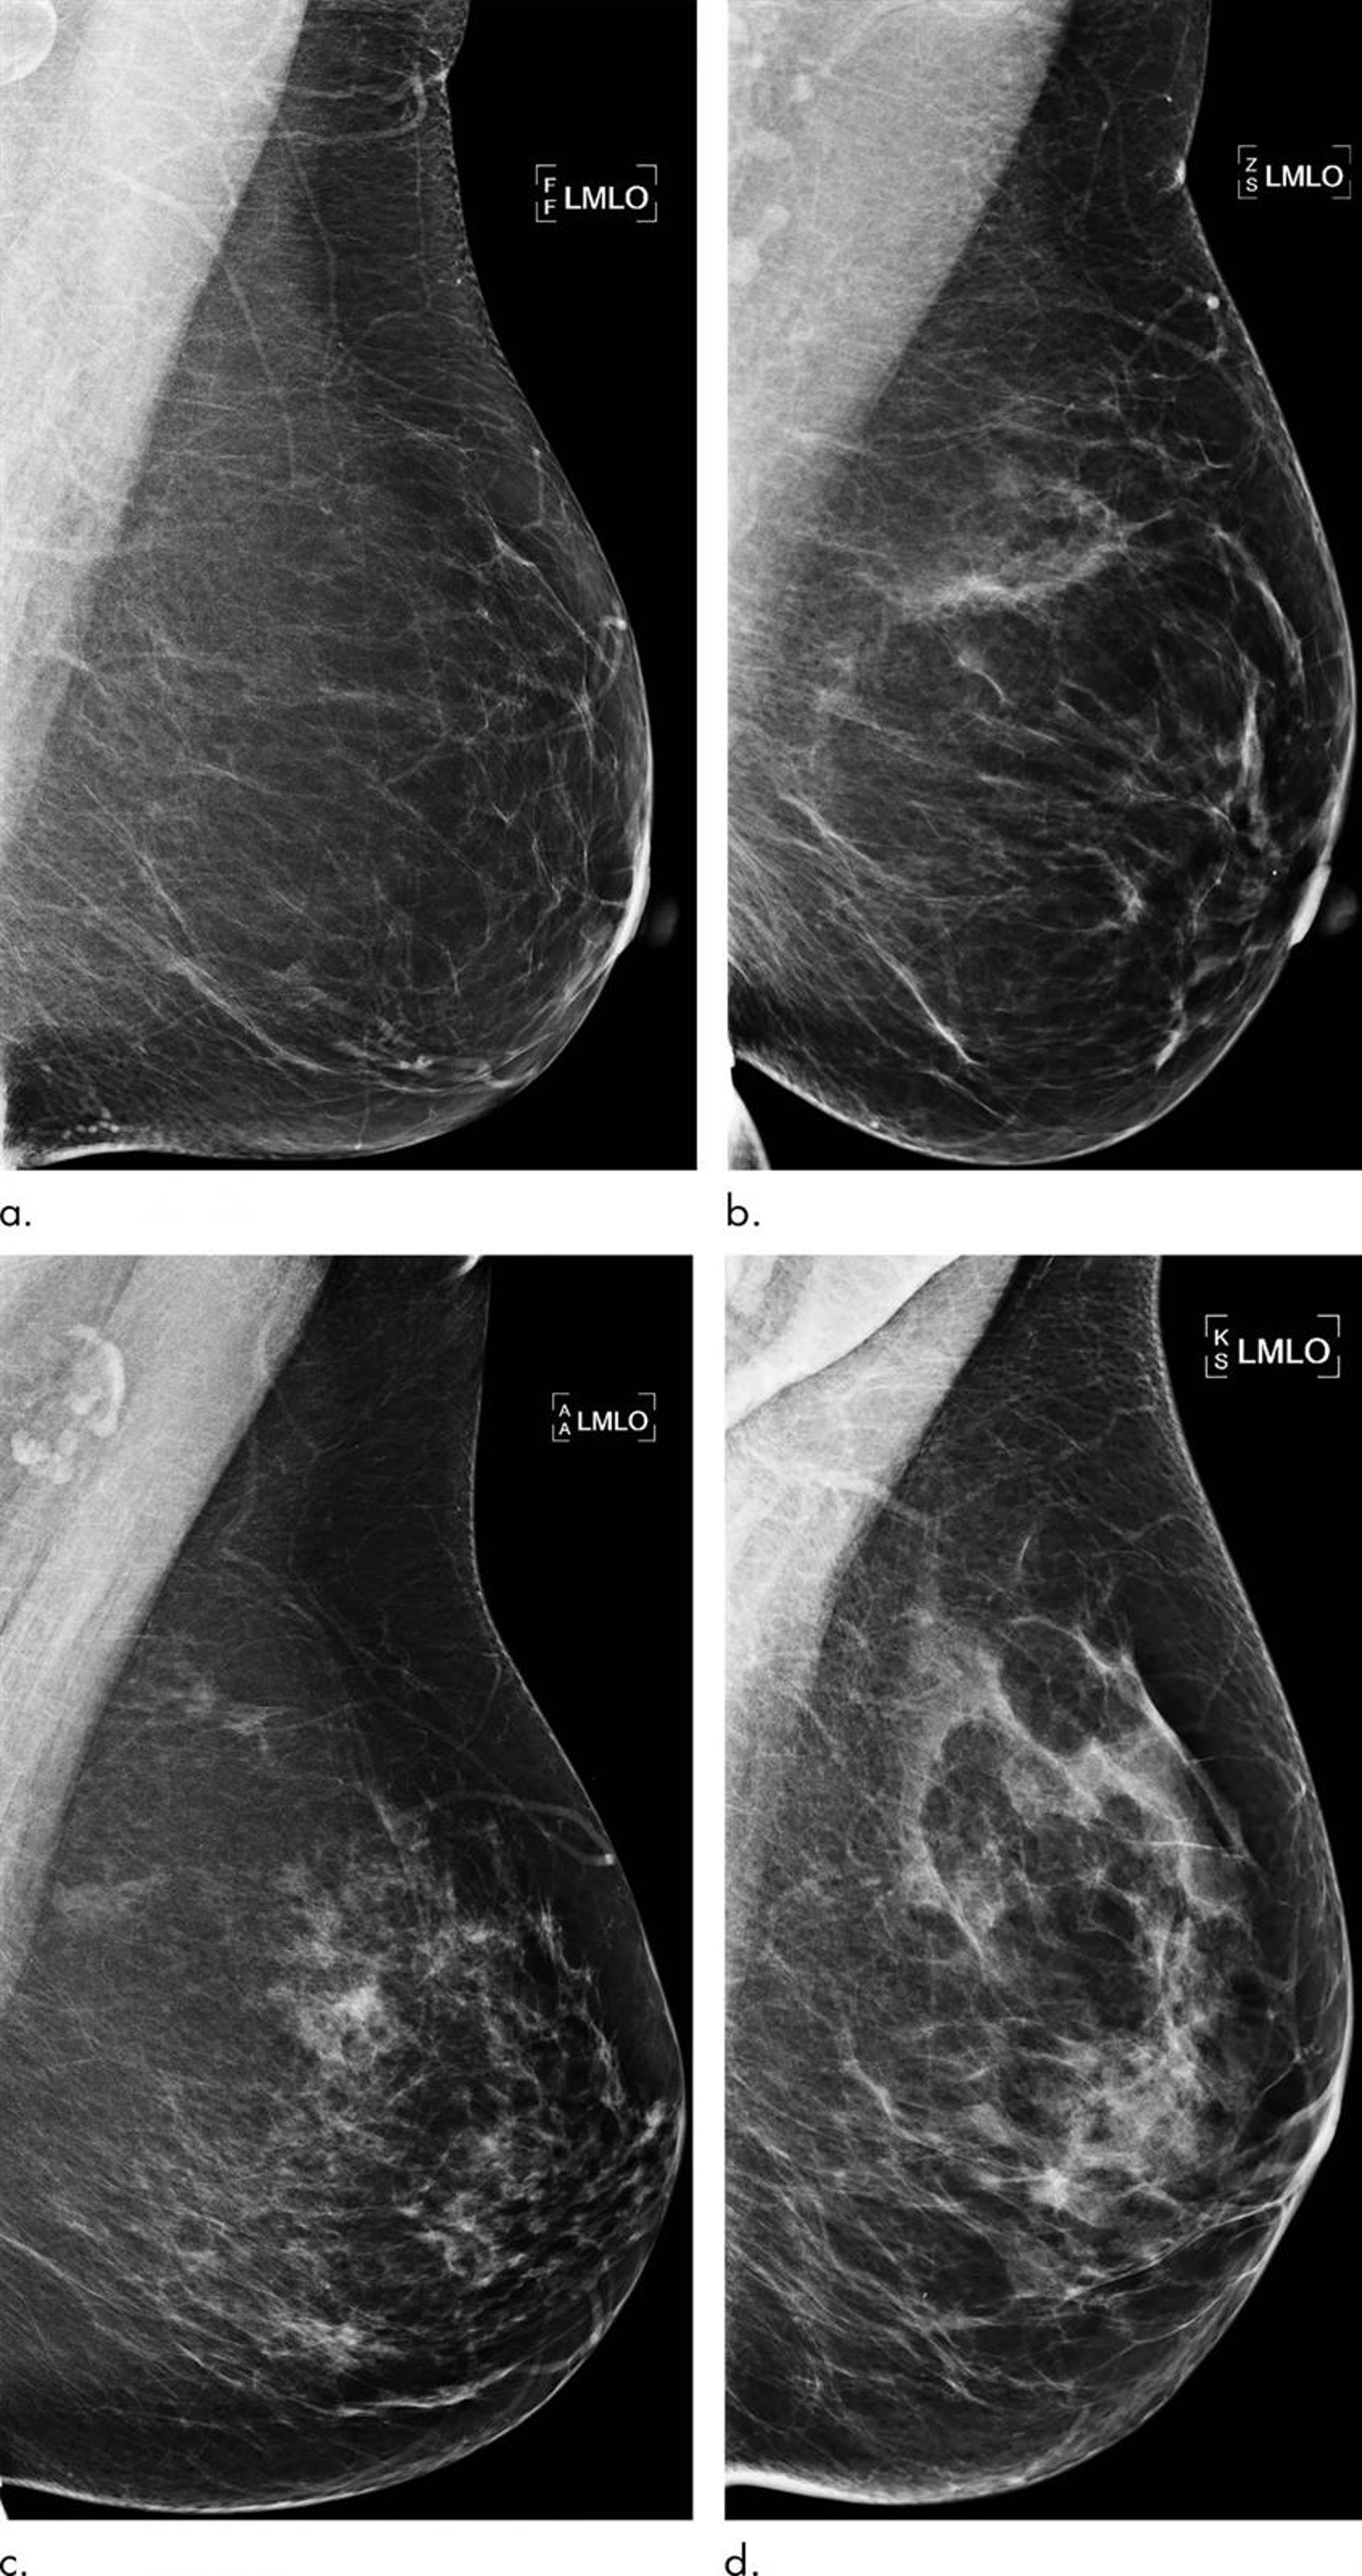

Ejemplos de mamografías con concordancia entre el puntaje de riesgo de aprendizaje profundo y el resultado del cáncer de seno (predicciones verdaderas).

Ejemplos de mamografías con concordancia entre el puntaje de riesgo de aprendizaje profundo y el resultado del cáncer de seno (predicciones verdaderas). - RADIOLOGICAL SOCIETY OF NORTH AMERICA